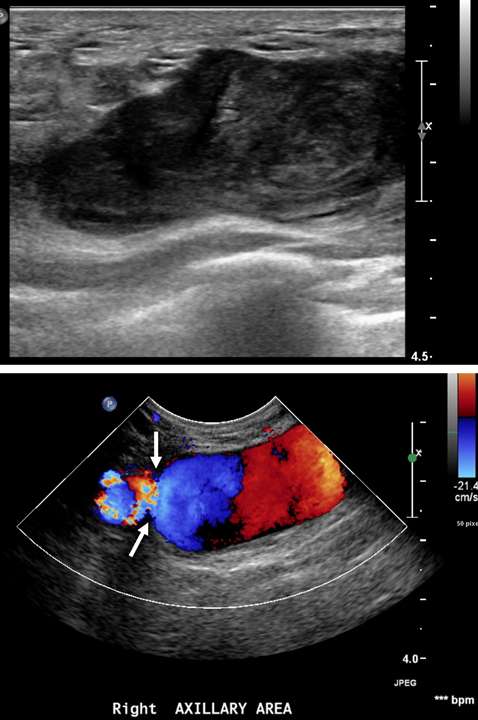

Figure 5A. Pseudoaneurysm. A 55-year-old woman who recently underwent ultrasound-guided biopsy of a right upper outer quadrant breast mass was noted to have an expanding hematoma on physical exam. Greyscale (top) and color Doppler (bottom) ultrasonography over the biopsy site revealed a large heterogenous fluid collection with internal to-and-fro flow and a positive “yin-yang” sign, consistent with a pseudoaneurysm. The pseudoaneurysm was seen arising from a branch of the right axillary artery and was associated with a relatively narrow neck (arrows). Interventional radiology was consulted for further management.